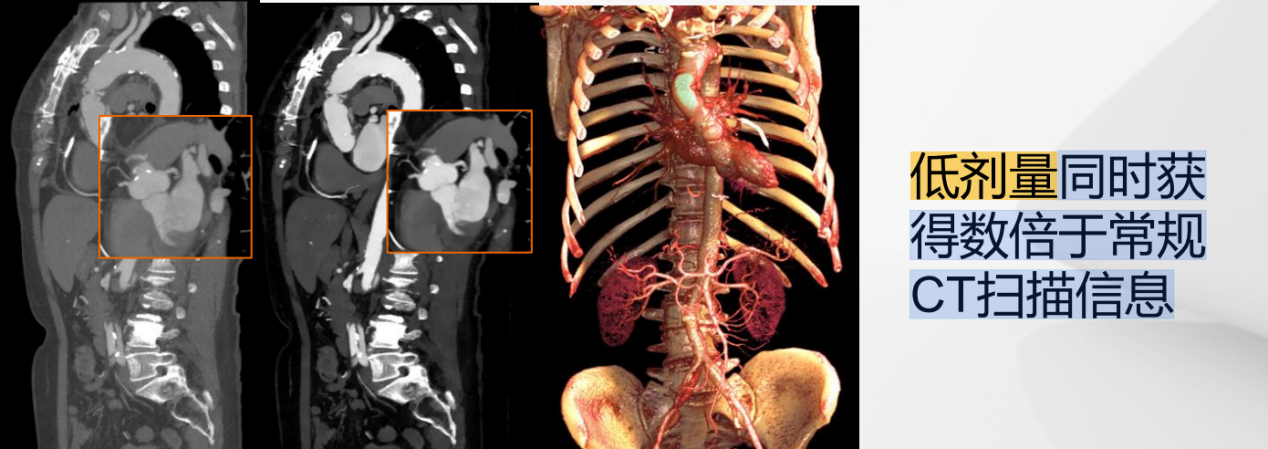

(1)超低剂量扫描:低辐射剂量+低对比剂用量的同时获得数倍于常规CT扫描信息。